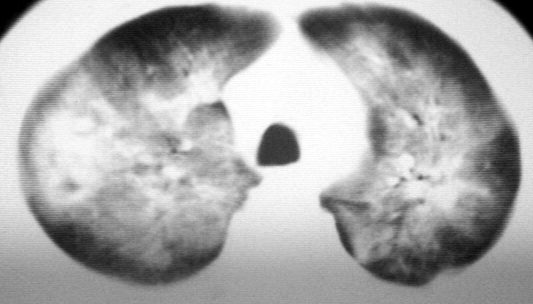

双肺内中部见略不对称性蝶翼状高密度区,边界不清,部分呈磨玻璃样密度,并可见含气支气管征。肺门、纵隔内未见肿大淋巴结影。无胸腔积液。

考虑:1、肺炎,建议进一步查冷凝集试验除外支原体肺炎;

2、不除外霉菌感染。

双肺斑片状密度均匀病灶,边界模糊可见充气支气管征,上野多于下野,不支持结核,1肺内感染,2查肾功,中心型肺水肿待除外.

双肺中上野对称分布蝶翼样不均匀密度增高影,有支气管充气征,纵隔未见肿大淋巴结,发病突然,抗炎治疗无效,还是要考虑结核。

还是考虑肺水肿!蝶翼征.肺门增大,肺血管影增粗,!!病变累及中内带为主!要排外支原体感染.

支持: 双肺内中部见略不对称性蝶翼状高密度区,边界不清,部分呈磨玻璃样密度,并可见含气支气管征。肺门、纵隔内未见肿大淋巴结影。无胸腔积液。